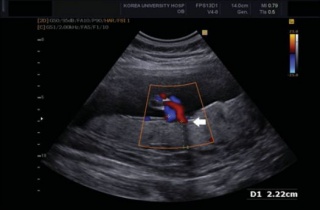

°í·Á´ëÇб³ ¾È¾Ïº´¿ø »êºÎÀΰú ¾È±âÈÆ ±³¼öÆÀ(¾È±âÈÆ·È«¼øÃ¶)ÀÌ ÅÂ¾Æ ¹ßÀ°Áö¿¬°ú °ü·ÃÇØ¼­ Á¶±â ¿¹ÃøÀÌ °¡´ÉÇÑ »õ·Î¿î µµ2017-06-28 17:45:48